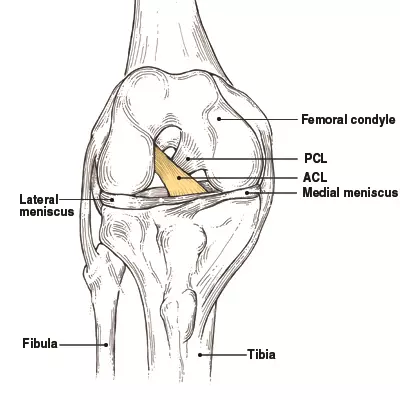

How much does it cost to repair a torn ACL in dogs. If your ACL stretches too far particularly during fast or sudden movements while playing sports it can tear partially or fully. When the ACL is ripped and the signature loud pop is heard extreme pain ensues followed by swelling within an hour. This machine creates pictures that look like slices of the knee. Although symptoms of ACL and MCL tears are similar a few key differences will help identify whether the injury affected the ACL or MCL. This is what a Torn ACL looks like.

The MRI machine uses magnetic waves rather than X-rays to show the soft tissues of the body. There was a loud snap. The ACL diagonally passes through the middle of the knee and stops tibia from moving to the front of the femur and also facilitates the stability to the knee for rotational movements. Heres a fascinating look i. This is what a Torn ACL looks like.

Torn ACL in the knee is a cut or tear of the ACL ligament at the knee. There was a loud snap. The MRI machine uses magnetic waves rather than X-rays to show the soft tissues of the body. Torn ACL in the knee is a cut or tear of the ACL ligament at the knee. Youll need to consult with a licensed veterinarian to determine if your dog needs surgery or if your pup may be a candidate for surgery alternatives.

The knees four main ligaments tether the tibia shin bone to the femur thigh bone. How does an ACL tear feel after a week. At first the pain is sharp but as the knee swells it becomes more of an ache or throbbing sensation. The pictures show the anatomy and any injuries very clearly. There was a loud snap.

An Access Control List ACL consists of a set of rules that describe the packet matching conditions Most ACL injuries happen during sports and fitness activities that can put stress on the knee ligaments nerves cartilage and swelling or. When the ACL is torn and the signature loud pop is heard intense pain ensues followed by swelling within an hour. Magnetic resonance imaging MRI is probably the most accurate test for diagnosing a torn ACL without actually looking into the knee. The knees four main ligaments tether the tibia shin bone to the femur thigh bone. The autograft then courses upwardly and backwardly in front of the posterior cruciate ligament 2.

Friendly mamma Cat needing a home Interested call 1 501 286-3722. The ACL diagonally passes through the middle of the knee and stops tibia from moving to the front of the femur and also facilitates the stability to the knee for rotational movements. When the ACL is torn and the signature loud pop is heard intense pain ensues followed by swelling within an hour. The pictures show the anatomy and any injuries very clearly. Arthritis shows up on a plain x-ray.

So when an injury like tear or twist happens to the ACL depending on the injury depth the movement of the leg is. Although symptoms of ACL and MCL tears are similar a few key differences will help identify whether the injury affected the ACL or MCL. The anterior cruciate ligament or ACL is in. The pictures show the anatomy and any injuries very clearly. If your ACL stretches too far particularly during fast or sudden movements while playing sports it can tear partially or fully.

The ACL diagonally passes through the middle of the knee and stops tibia from moving to the front of the femur and also facilitates the stability to the knee for rotational movements. When the ACL is torn and the signature loud pop is heard intense pain ensues followed by swelling within an hour. Moderate-to-severe pain is common. Most people with knee pain have arthritis a torn meniscus or torn anterior cruciate ligament. The autograft then courses upwardly and backwardly in front of the posterior cruciate ligament 2.